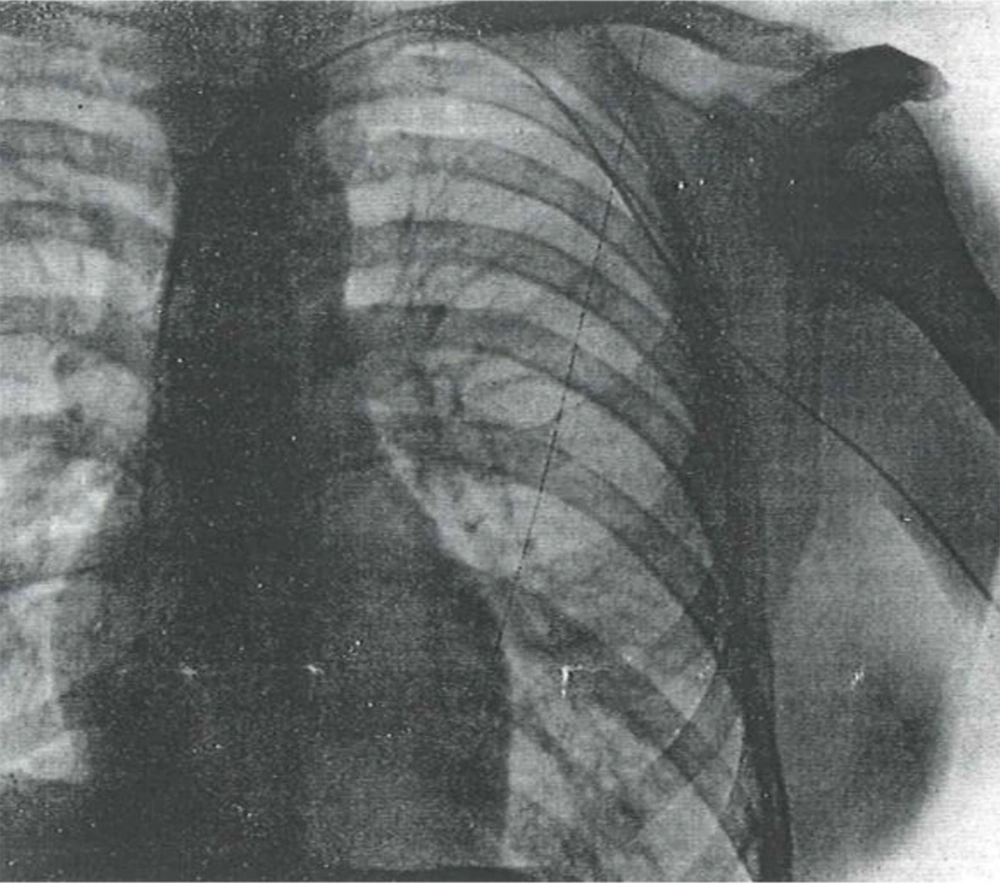

A bold experiment that changed medicine forever. Werner Forssmann became the first person to catheterize a living human heart—his own.

Werner Forssmann was only twenty-five when he began imagining a way to reach the human heart from the inside. While working as a young physician at Auguste-Viktoria Hospital in Germany, he often performed autopsies and noticed that although the body could appear intact, the heart frequently told the real story of death—damaged valves, malformed chambers, and blocked vessels. At the time, heart disease was something doctors could only observe after death, not treat in the living. Inspired by earlier veterinary experiments, Forssmann believed a thin tube could be inserted through a vein and guided safely to the heart, allowing doctors to diagnose and eventually treat cardiac disease. Many physicians considered the idea too dangerous, but Forssmann was determined to prove otherwise.

In 1929, after receiving permission to experiment only on animals, Forssmann decided to test the idea on himself. With the help of an operating room nurse, Gerda Ditzen, he secretly inserted a catheter into a vein in his own left arm and carefully advanced it toward his heart. To confirm the experiment, he walked two flights of stairs to the radiology department with the catheter still inside his body and captured an X-ray showing the tube reaching his heart. That image became the first successful demonstration of cardiac catheterization in a living human. Though risky at the time, Forssmann’s daring experiment opened the door to modern cardiology, making it possible for physicians to explore, diagnose, and treat the heart from within.